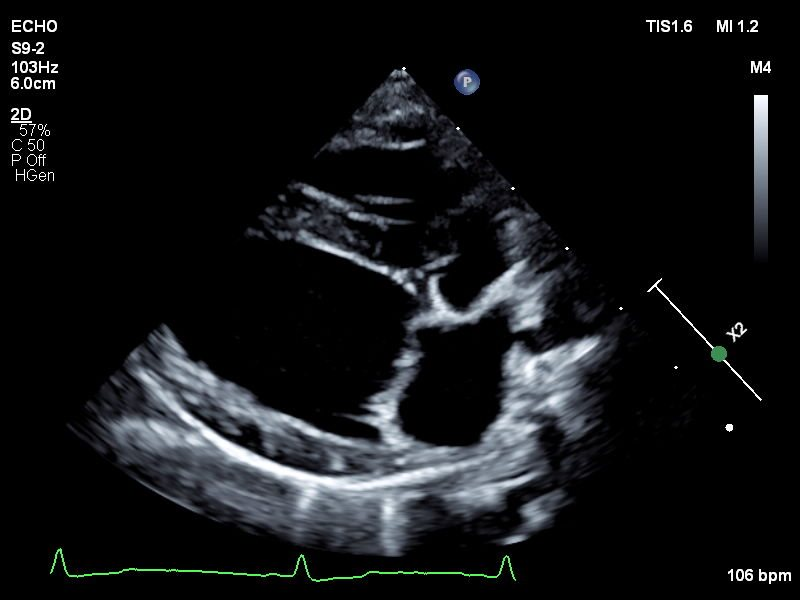

Echocardiograms

Veterinary echocardiography is a type of ultrasound imaging that focuses on the heart. Echocardiography assesses the structure and function of an animal's heart. This non-invasive procedure employs ultrasound technology to produce detailed, real-time images of the heart's chambers, valves, and blood flow. Echocardiography is essential for diagnosing and monitoring heart conditions such as heart murmurs, cardiomyopathy, and valve disorders. It helps veterinarians evaluate the severity of heart disease, guide treatment decisions, and monitor the effectiveness of therapies, all while ensuring the animal's comfort and safety.